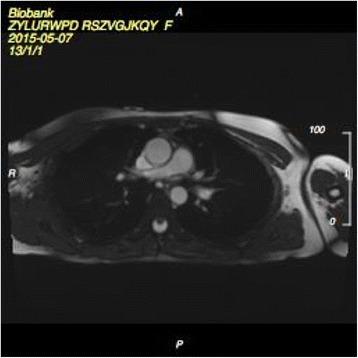

UK Biobank's cardiovascular magnetic resonance protocol.

METHODS/DESIGN: We describe the CMR protocol applied in UK Biobank's pilot phase, which will be extended into the main phase with three centres using the same equipment and protocols. The CMR protocol includes white blood CMR (sagittal anatomy, coronary and transverse anatomy), cine CMR (long axis cines, short axis cines of the ventricles, coronal LVOT cine), strain CMR (tagging), flow CMR (aortic valve flow) and parametric CMR (native T1 map).

方法/设计:我们描述了英国生物银行试点阶段所应用的CMR方案,该方案将在三个使用相同设备和方案的中心扩展到主要阶段。CMR方案包括白血CMR(矢状位解剖、冠状动脉和横断位解剖)、电影CMR(长轴电影、心室短轴电影、冠状位左心室流出道电影)、应变CMR(标记)、血流CMR(主动脉瓣血流)和参数化CMR(固有T1图谱)。